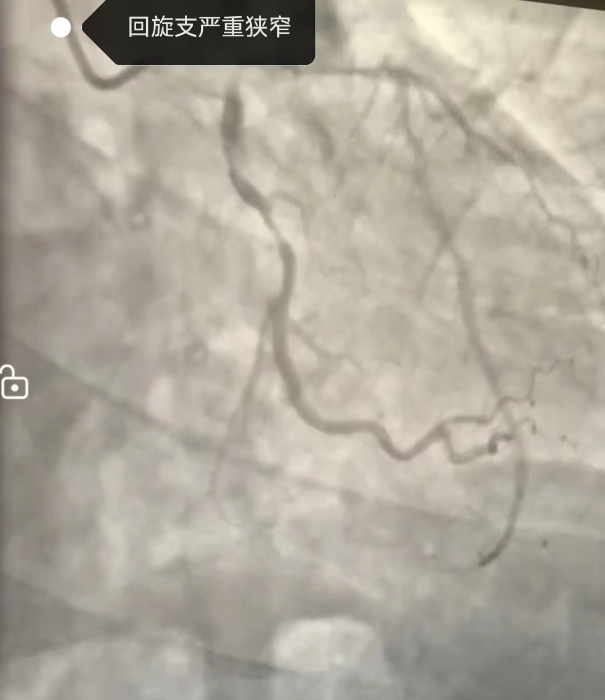

經冠脈造影(yǐng)提示:劉某冠狀動脈鈣化,左回旋支有90%以上的彌漫狹窄,手術(shù)成功植入2枚支架,解決了血管狹窄的問(wèn)題。術(shù)後,血液淨化室主任楊奕合理(lǐ)安排,及時爲劉某進行了血液透析。劉某術(shù)中、術(shù)後無不适,胸悶及胸痛症狀緩解,目前已出院。